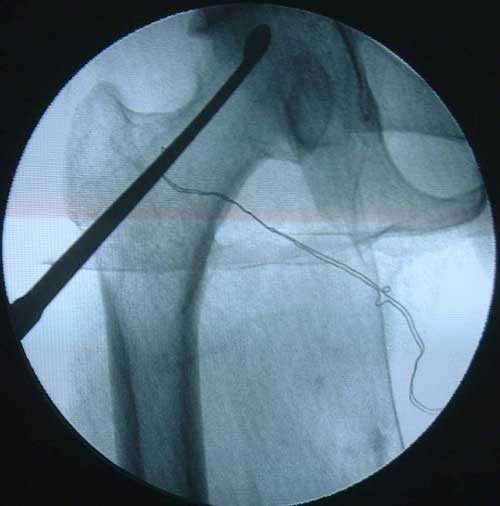

• 采用隧道减压、死骨刮除、骨形态发生蛋白植入、异体腓骨支撑治疗股骨头坏死,获得良好疗效。

BMP植入,异体骨支撑,恢复形态     手术后24个月X线片,关节塌陷未加重,关节功能良好,无疼痛